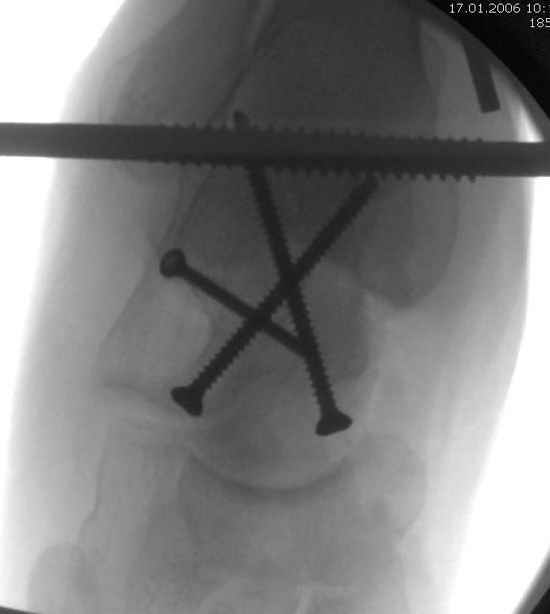

Вдогонку по поводу перелома таранной кости, больная 81, не страдает диабетом, перелом закрытый, в первый же день поступления ограничились временным наружным фиксатором (как на снимке).

Планировалась открытая фиксация после спадения отека, но больная пожелала лечиться по месту жительству в другом штате..

За пару недель насчитал 5 больных с переломом таранной кости, из них двое с двусторонним повреждением.

Из-за отека на стопе тактика лечения у всех была

одинаковая: временная наружная фиксация до спадения отека, при изолированных переломах они выписывались домой и через дней 7 госпитализировались на оперативное лечение.

Примеры на снимке...